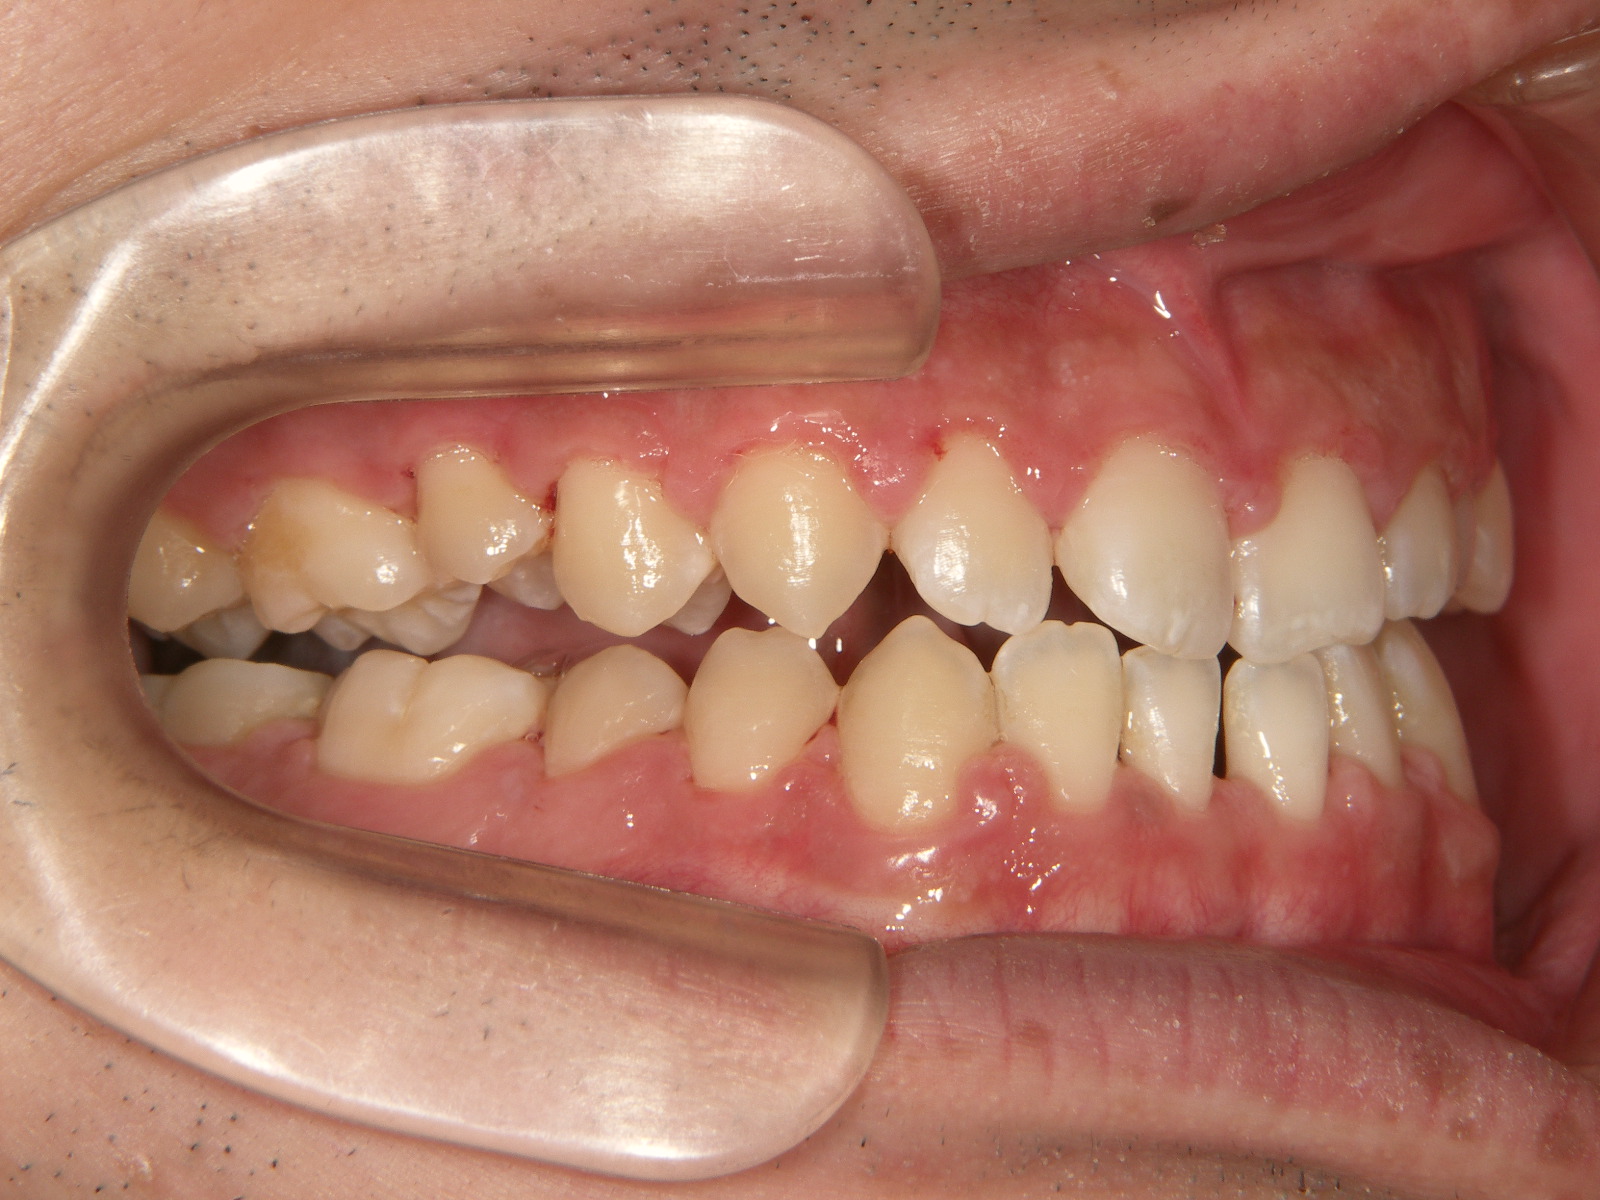

②外科手術後

外科手術後の状態です。下顎の位置は下がり、受け口が改善されましたが、上下のかみ合わせのズレがあります。